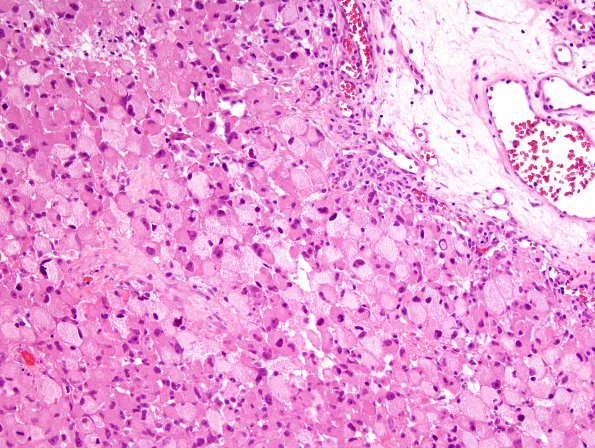

Washington University Experience | NEOPLASMS (GLIAL) | Glioblastoma, granular cell type | 7B2 GBM (Case 7) H&E 2

7B2-4 The tumor has a variety of different morphological appearances varying from epithelioid, often foamy cells, to spindle shaped cells in some areas. Frequent mitoses and extensive endothelial cell proliferation are identified.